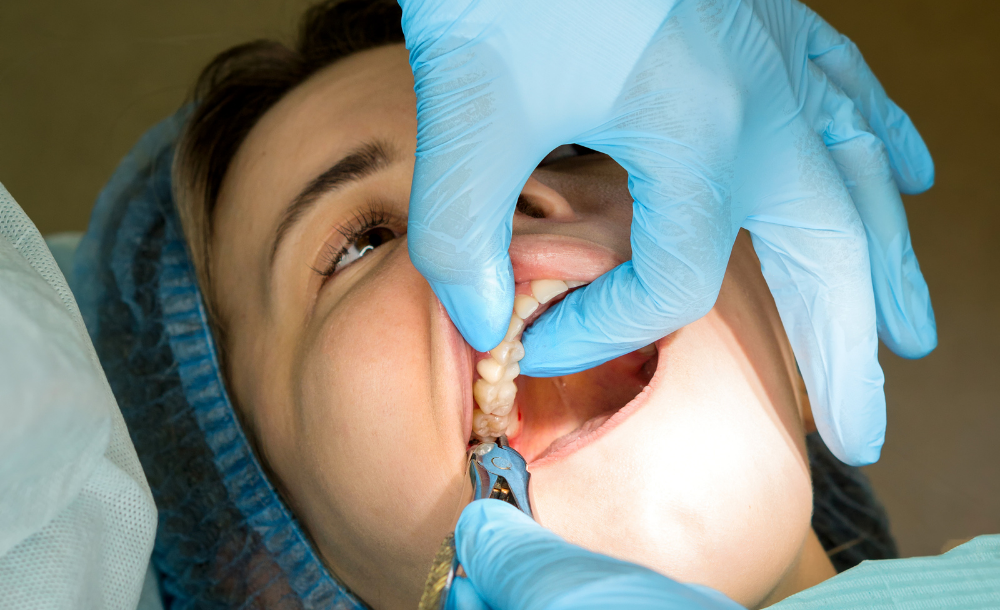

Local Anesthesia / Sedation – Ensuring a pain-free experience

Gentle Extraction – Using advanced techniques for quick recovery